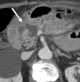

Postoperative fluid collection

A lymphocele is a collection of lymphatic fluid within the body not bordered by epithelial lining. It is usually a surgical complication seen after extensive pelvic surgery (such as cancer surgery) and is most commonly found in the retroperitoneal space. [Source: Wikipedia ]